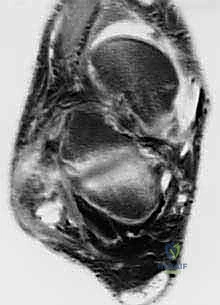

- MRI of the involved ankle: This is invaluable. It demonstrates chronic thickening, fissuring, scarring, and stenosis of the remaining peroneal structures. We'll look for tears within the tendon substance and fluid in the sheaths, which are hallmarks of chronic tendinopathy. Associated ankle pathology, such as osteochondral lesions or ligamentous instability, must also be identified.